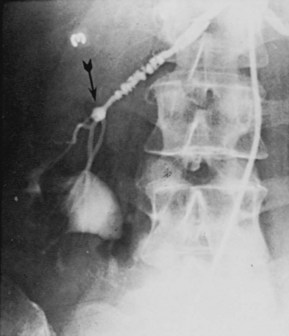

Angiography in primary intimal fibroplasia reveals a smooth, fairly focal stenosis, usually involving the proximal or midportion of the vessel or its branches (Fig. 39–3). Dissecting hematomas may distort the area of the stenosis. With nonoperative management, progressive renal artery obstruction and ischemic atrophy of the involved kidney invariably occur. Severe intimal fibroplasia may subsequently develop de novo in the contralateral renal artery. Although primary intimal fibroplasia most commonly affects the renal arteries, it may also occur as a generalized disorder with concomitant involvement of carotid, upper and lower extremity, and mesenteric vessels.

Angiographically, medial fibroplasia demonstrates a typical “string of beads” appearance involving the distal two thirds of the main renal artery and branches (Fig. 39–4). The areas of stenosis are often overshadowed by contrast medium in the microaneurysms, making the degree of actual stenosis difficult to assess. The aneurysms themselves are greater in diameter than the normal renal artery proximal to the disease, and extreme collateral circulation is absent. These are important features in differentiating the lesion from perimedial fibroplasia. Schreiber and colleagues (1984) studied the natural history of renal artery disease due to medial fibroplasia in 66 patients who were followed with serial angiography. Progressive renal artery stenosis (RAS) occurred in 22 patients (33%), and, contrary to an earlier report, this occurrence was no different whether patients were older or younger than 40 years. Significantly, there were no cases of progression to total arterial occlusion in this group. Also, clinical follow-up revealed that serial decreases in either overall renal function or the size of the involved kidney seldom occurred in patients with progressive medial fibroplasia, suggesting that the risk of losing renal function is relatively small in patients with this disease who are managed medically.

Figure 39–4 Selective right renal arteriogram reveals medial fibroplasia involving the main renal artery with typical “string of beads” appearance.

(From Novick AC. Renal vascular hypertension in children. In: Kelalis PP, King LR, Belman AB, editors. Clinical pediatric urology. Philadelphia: WB Saunders; 1984.)

The arteriogram in perimedial fibroplasia may give the appearance of arterial beading, but careful observation shows that the caliber of the normal segment of the vessel is not exceeded by the “bead” (Fig. 39–6). This fact, along with the frequent occurrence of extensive collateral circulation, differentiates this lesion angiographically from that of medial fibroplasia. Perimedial fibroplasia produces severe stenosis, and, although complicating thrombosis or dissection is relatively uncommon, progressive obstruction with ischemic renal atrophy occurs in almost all patients managed nonoperatively.

Figure 39–6 Renal arteriogram in a patient with perimedial fibroplasia shows slightly irregular, yet severe, stenosis of the midrenal artery (arrows) associated with extensive collateral circulation to the kidney. The small size of the arterial irregularities and the presence of collateral circulation distinguishes this lesion radiographically from medial fibroplasia.